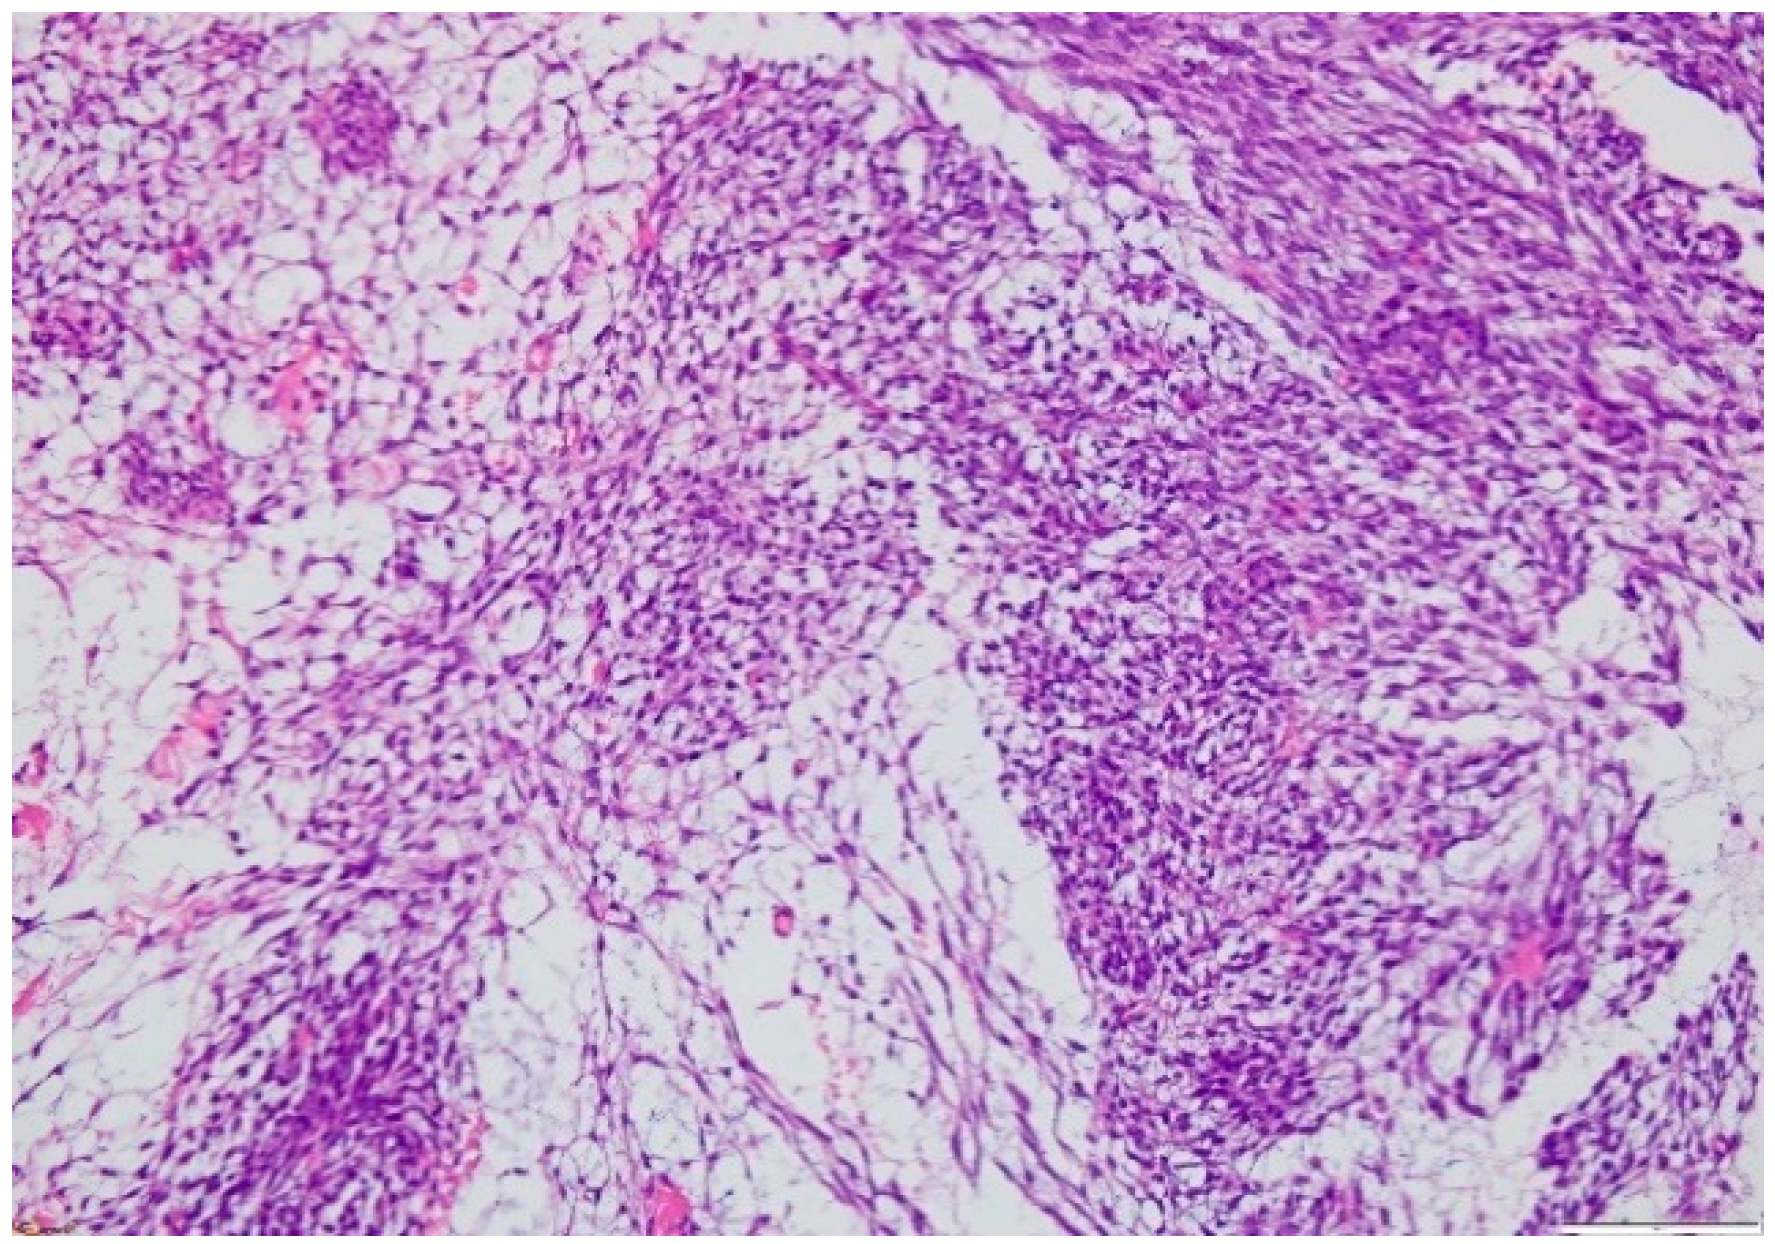

2.3. Biopsy